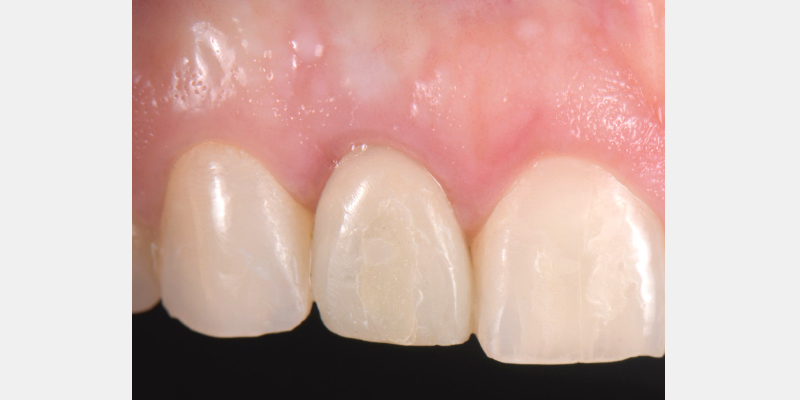

One of the most common complications with cement-retained implant restorations is inflammation around the crown. Excess cement can lead to peri-implant diseases such as peri-implant mucositis and even bone loss. A key factor to understand is the biological difference between teeth and implants — particularly the structure of the junctional epithelium and connective tissue — which makes removing residual cement around the restoration more difficult.

Here is a simple, step-by-step technique for fabricating a silicone jig to avoid excess cement in a cement-retained implant-supported restoration. It can be applied to a single crown or to an implant-supported cement-retained bridge.